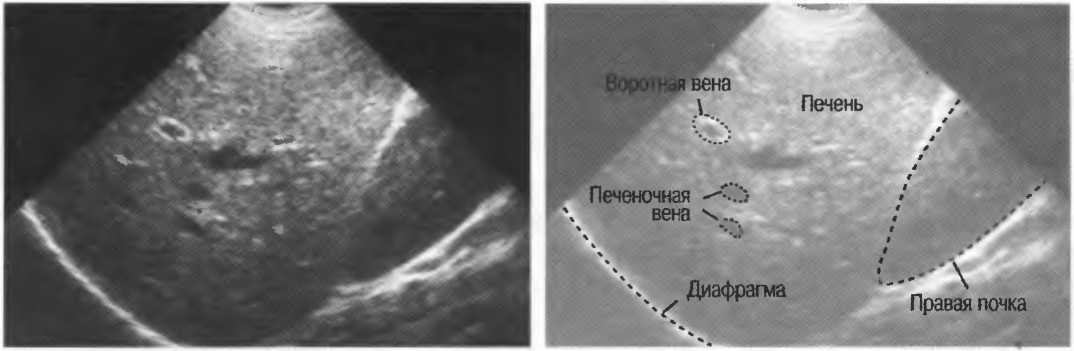

Диафрагму. |

|

8. |

Мочевой пузырь (если он наполнен). |

|

9. |

Органы малого таза. |

Если заподозрена патология, обращайтесь к соответствующим разделам данного руководства.

ГЛАВА 6

Брюшная аорта

Показания к исследованию

Подготовка